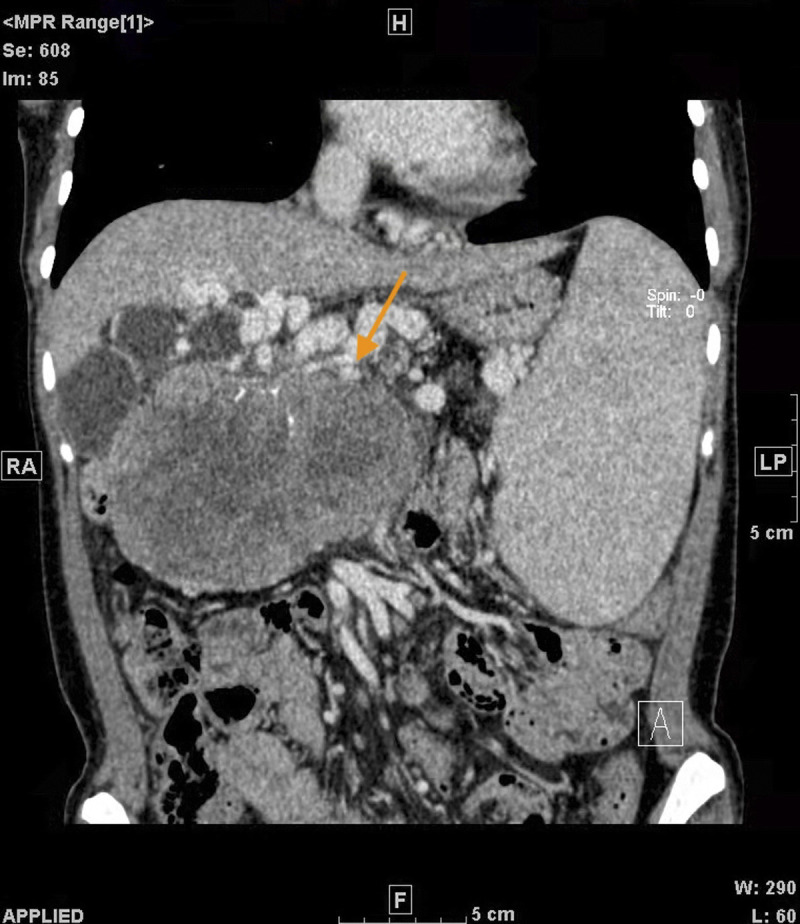

Pregnancy with solid pseudopapillary tumor of the pancreas (SPTP) is rare. Because pregnancy hormones may cause tumor progression, the management and treatment of SPTP need to balance the safety of pregnant women and fetuses with surgical treatment. We reported a case of a giant pancreatic tumor diagnosed during pregnancy that was considered to be SPTP. Examinations also showed hepatitis B virus infection and severe decompensation of liver cirrhosis. Medical termination of pregnancy was performed. The patient has lived with the tumor until now without surgery. We retrieved the published case reports, summarized the clinical characteristics of pregnancy with SPTP, and explored its management during the perinatal period. Most patients with SPTP have a good prognosis with good maternal and fetal outcomes, and it is important to choose an appropriate treatment method and timing. However, pregnancy combined with decompensated liver cirrhosis needs to be terminated in a timely manner because of its high-risk status.